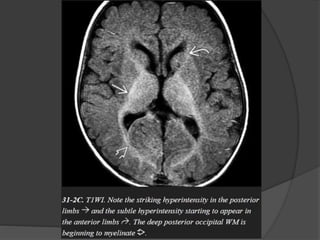

 Normal myelination… Hyperintense on T1 &

Hypointense on T2.

 Occipital subcortical U fibers.